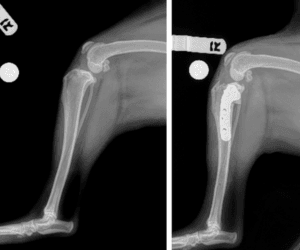

Cranial Cruciate Ligament Repair

The TPLO (Tibial Plateau Leveling Osteotomy) surgery has become one of the most common and effective orthopedic surgeries performed on dogs who have torn their cranial cruciate ligament. The philosophy behind the TPLO surgery is to completely change the dynamics of the dog’s knee so that the torn ligament becomes irrelevant to the stability of the knee itself. When a dog tears its ACL, every time the dog stands or puts weight on the leg, the femur slides/rubs on the back of the tibia. This rubbing causes pain and inflammation, which is very uncomfortable. This is why most dogs with a torn ACL will not put any weight on the leg, or if they do, they will just toe touch the leg to the ground. TPLO surgery works by altering the biomechanics of the knee, shifting the forces to the caudal cruciate ligament and eliminating the need for the ACL. The tibia osteotomy allows the tibial plateau to be rotated, then secured with a bone plate and locking screws that are sized for each individual pet. The new tibial plateau angle provides immediate stabilization to the knee and most patients are walking on the affected leg at or soon after discharge from the hospital.

Lateral Suture – $1750

Orthosta/Tightrope $2500

TPLO $3700

+$250 >100 lbs